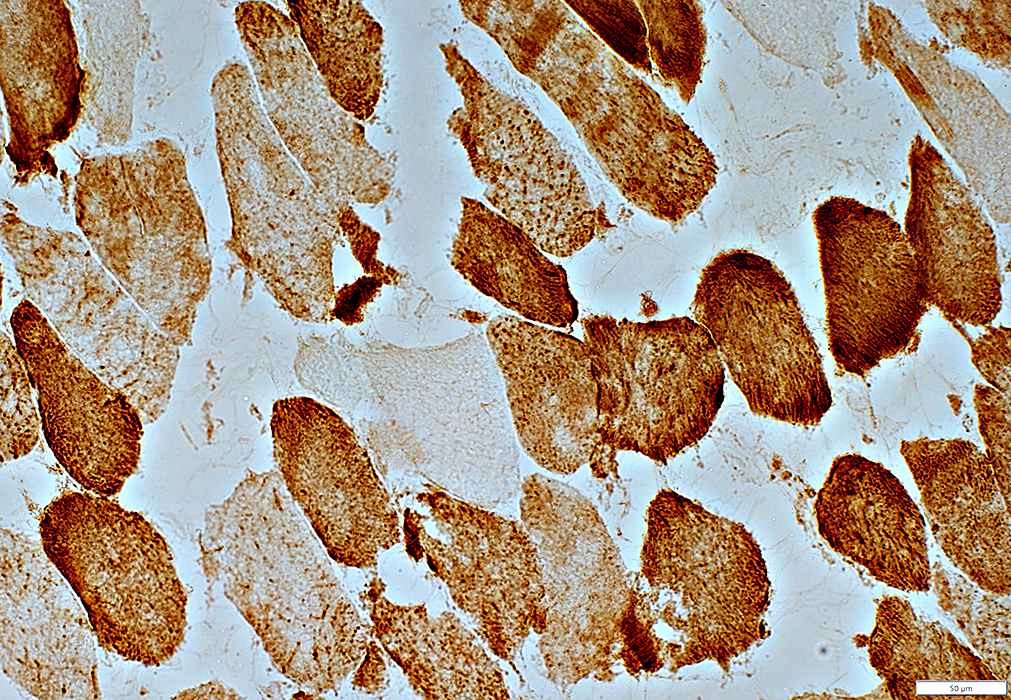

COX stain

COX negative muscle fibers

Muscle fibers with reduced staining

Mitochondria not visible